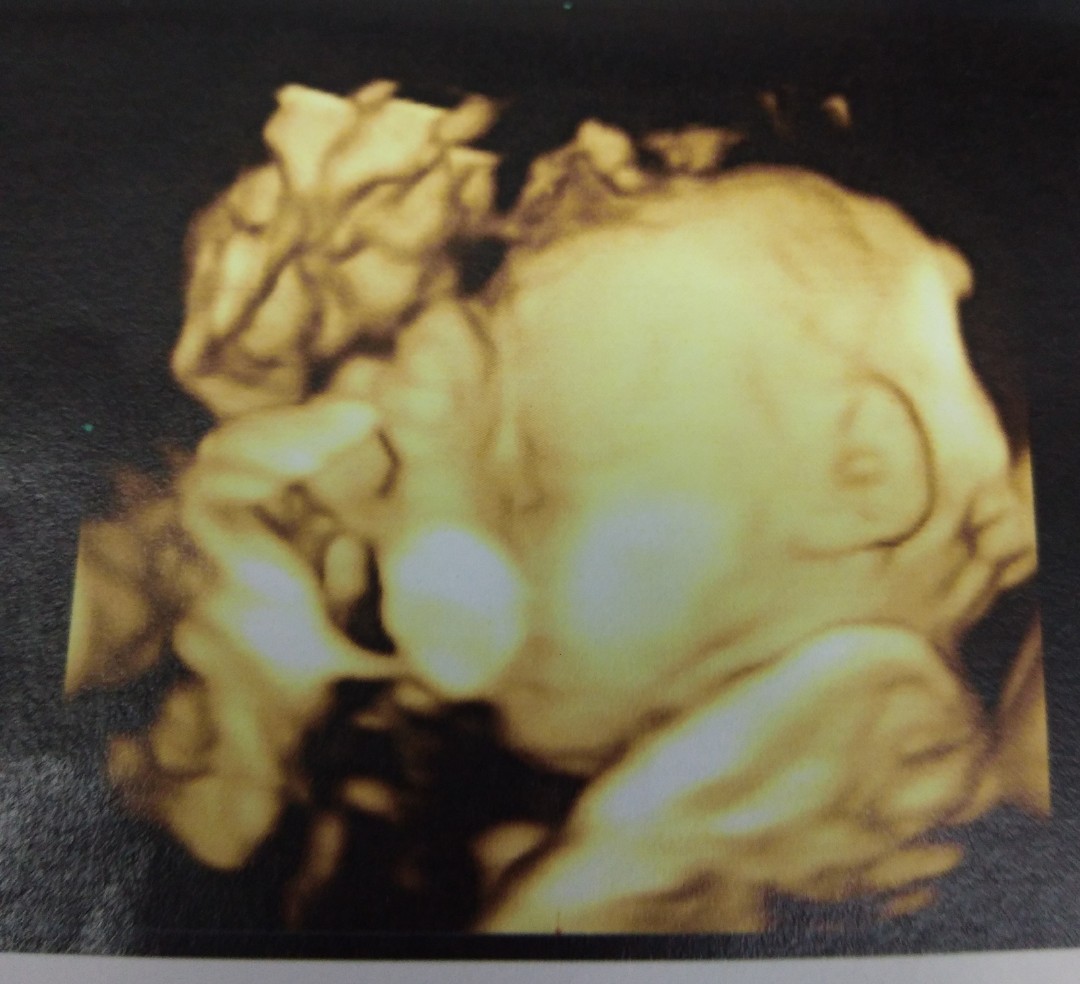

วันที่หมอนัด มีความสุขที่ได้เห็นหน้าลูก แม่บ้านไหนเป็นเหมือนบ้านนี้ไหมคะ

วันนี้หมอนัดตรวจ ป้าหมอบอกขอน้ำหนัก1โลพอ แต่น้ำหนักน้อง1,392 ตอนนี้28w3d. คลอด29ธันวา ผู้หญิงคะ

จมูกพุ่งมาก